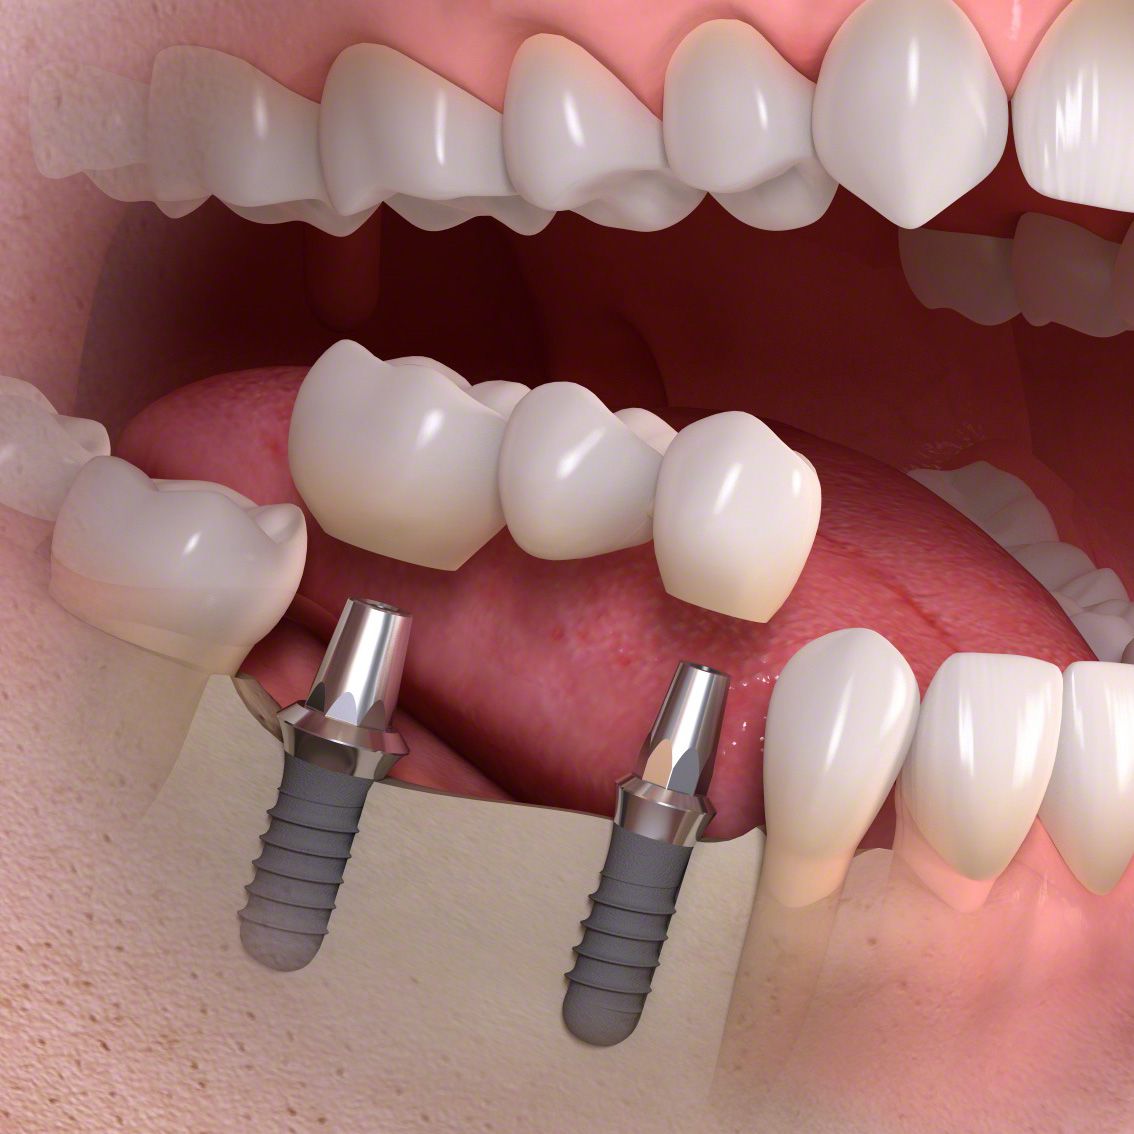

Die entstandene Lücke kann mit einer künstlichen Zahnwurzel, d.h. mit einem Implantat geschlossen werden. Implantate, meist aus Titan oder Keramik, werden dabei in einem kleinen chirurgischen Eingriff in den Kieferknochen eingesetzt. Nach dem Einheilen tragen sie später den eigentlichen Zahnersatz (Kronen, Brücken, Prothesen).

Implantate sind eine langlebige, festsitzende und komfortable Lösung und tragen damit zu mehr Wohlbefinden und Lebensqualität bei. Allerdings brauchen Sie besondere Aufmerksamkeit und Pflege: mit regelmäßiger Prophylaxe – alle 3 bis 4 Monate – werden Sie über viele Jahre Freude an Ihren neuen, festsitzenden Zähnen haben.